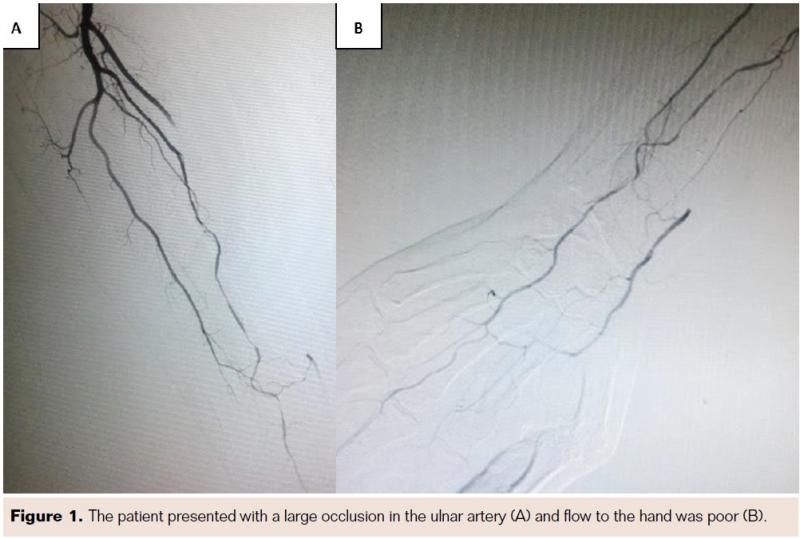

Angiography identified a total occlusion of the radial artery and an occlusion in the interosseous ulnar artery (Figure 1A) and flow to the hand was poor (Figure 1B). Endovascular intervention was performed in an effort to salvage the patient’s right hand and affected digits. Using the modified Seldinger technique, a 6 Fr sheath was placed in the brachial artery. A total occlusion in the right radial artery was crossed and treated by with 2.5 mm x 30 mm Apex balloon (Boston Scientific). Treatment resulted in less than 20% residual stenosis. Brisk anterograde flow was restored to the fingers and attention was turned to an occlusion in the interosseous ulnar artery (Figure 1A). A Prowater wire (Asahi) was used to transverse the stenosis. The Prowater wire was exchanged for a ViperWire (Cardiovascular Systems, Inc.) and a 1.25 mm (145 cm shaft length) Diamondback 360 Peripheral OAS (Cardiovascular Systems, Inc.) was advanced over the wire into the interosseous ulnar artery (Figure 2A). Sequential atherectomy passes were performed and the catheter was removed and exchanged for a tapering 2.5 mm x 210 mm NanoCross balloon (Covidien) (Figure 2B). Following balloon angioplasty, there was an improved angiographic result with restoration of flow into the hand and third and fourth fingers, as well as less than 30% residual stenosis of the interosseous ulnar artery (Figures 3A and 3B). However, flow to the diseased fingers was still poor, suggesting that necrosis was fairly advanced or additional occlusions were present within the digits. The procedure was well tolerated by the patient, with no acute procedural complications and positive angiography results were achieved at the conclusion of the interventions.